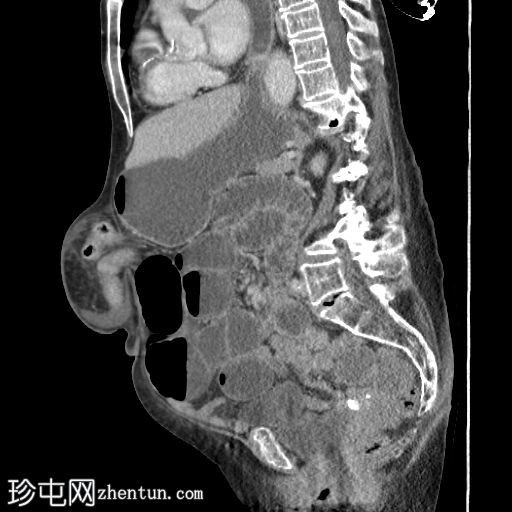

矢状位增强扫描(门静脉期)

3.jpg

可见一大型上腹疝,内含部分结肠,矢状位图像亦可见。